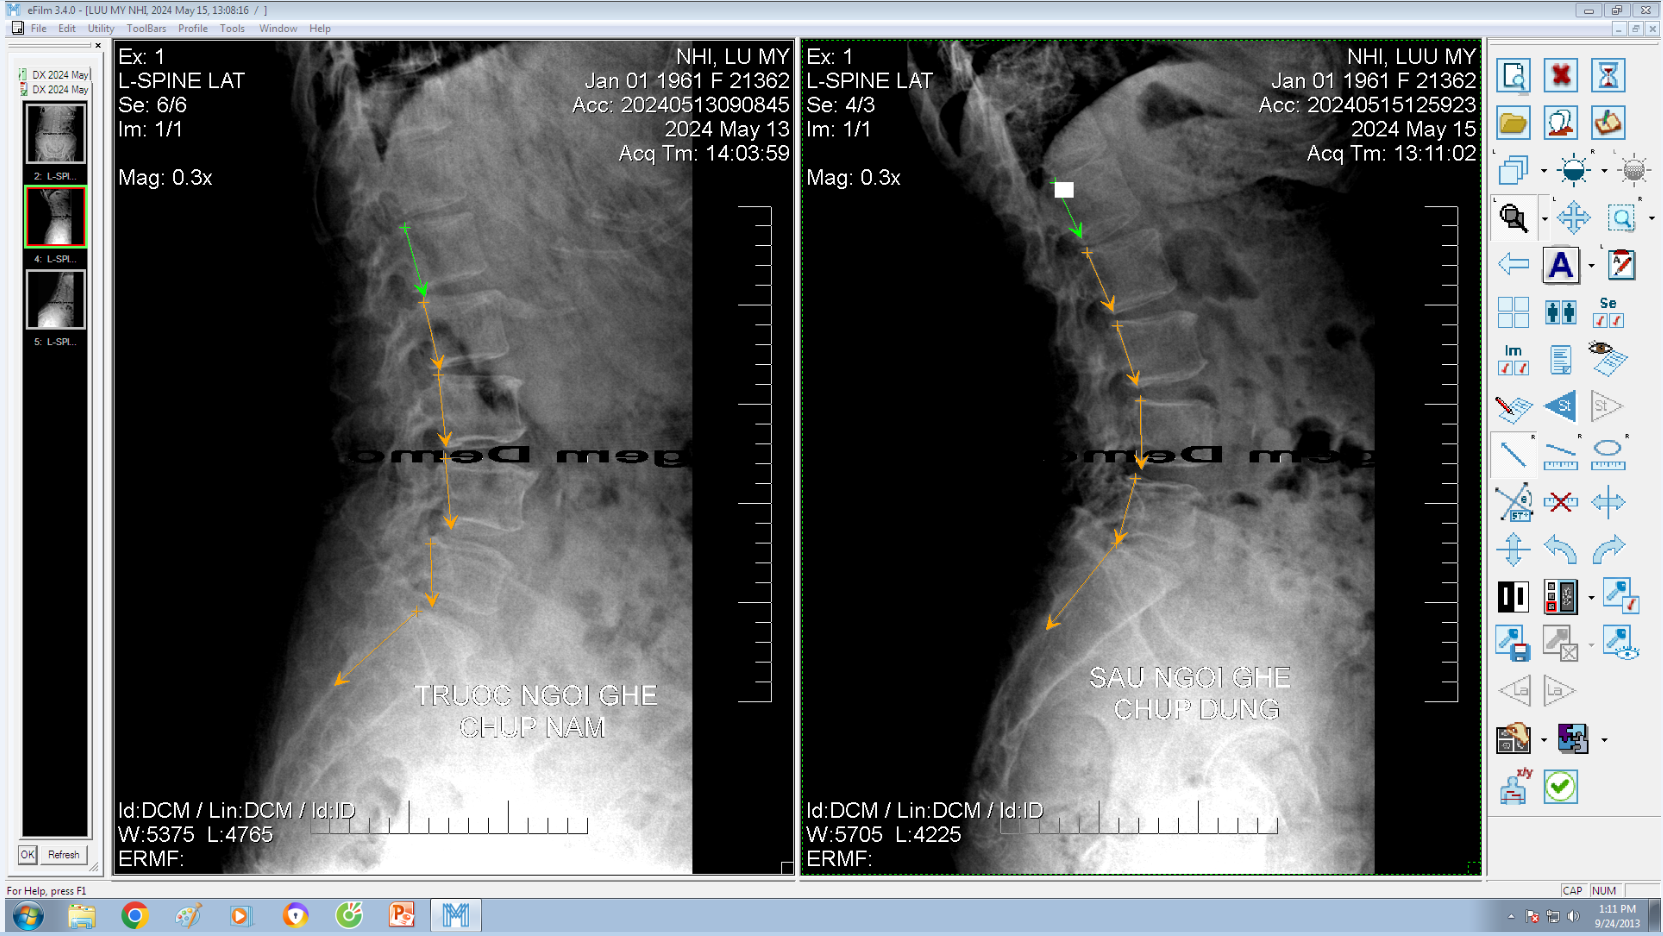

DOCTORLOAN đã thành công trong điều chỉnh xương khớp về đúng vị trí trong thời gian ngắn